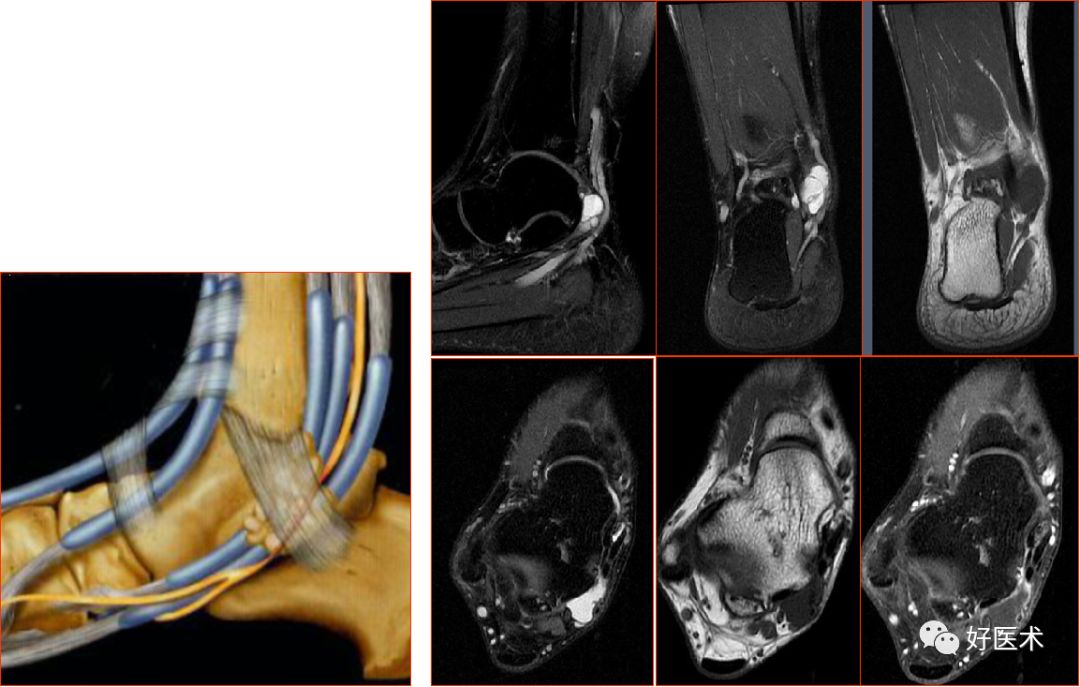

五、韧带损伤

踝关节的韧带

联合韧带

外侧副韧带

三角韧带

距跟韧带

胫腓前后韧带:位于胫距关节上方,连接外踝前、后面与胫骨前、后结节,起支持作用

胫腓横韧带:位于胫腓后韧带前下方,后外踝延伸至胫骨关节面后缘,恰好位于内踝的外侧

联合韧带(胫腓前韧带)撕裂

距腓前韧带

距腓前韧带撕裂

距腓后韧带

距腓后韧带部分撕裂

跟腓韧带

跟腓韧带急性完全撕裂